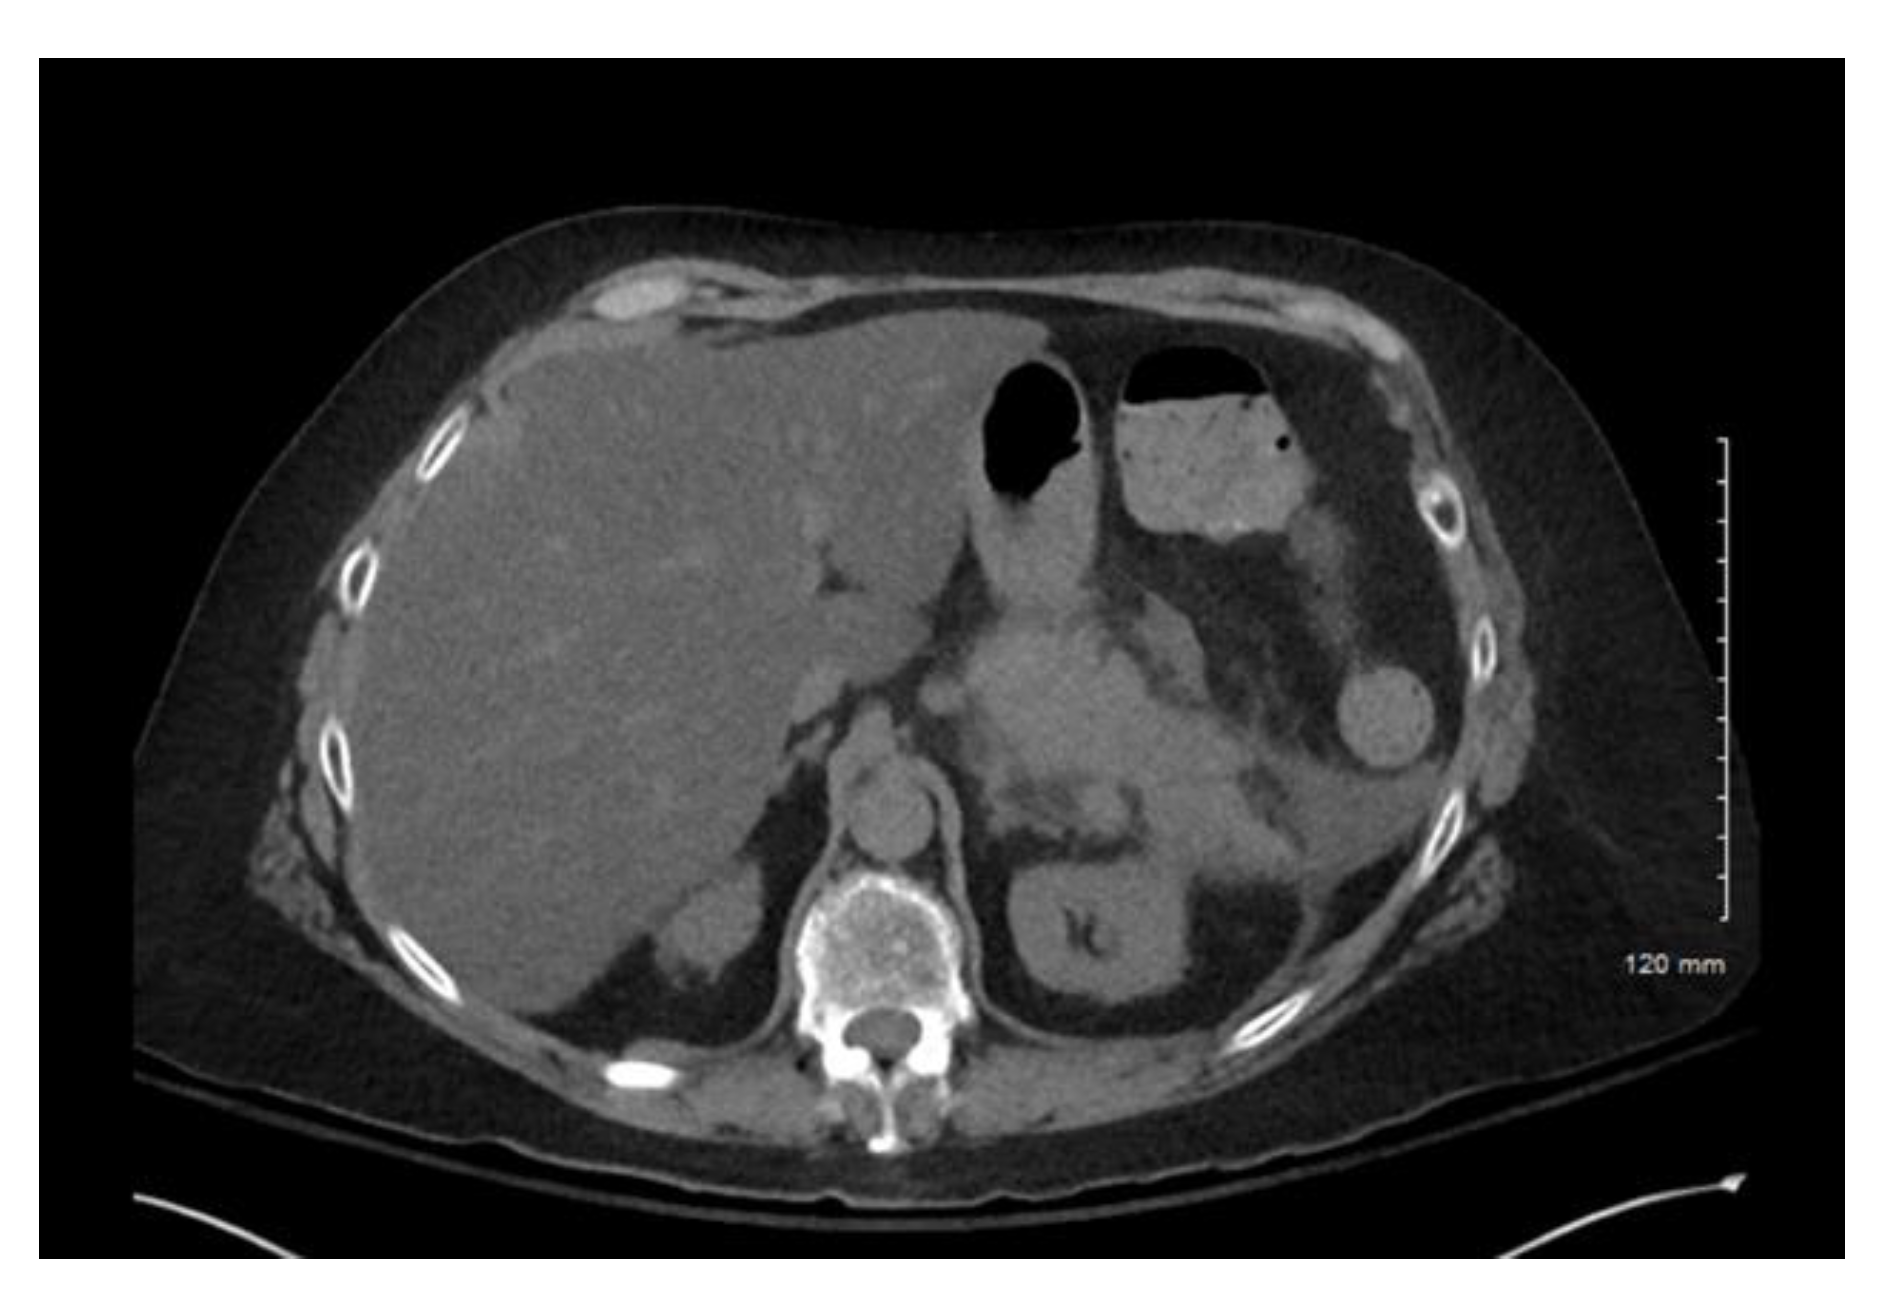

Computerized tomography (CT) of the abdomen and pelvis confirmed acute interstitial pancreatitis (Figure 1). No obvious necrosis or peripancreatic fluid was observed on imaging. Of note, a CT of the abdomen and pelvis, several weeks prior to this current presentation, revealed a normal-appearing pancreas. Lipase was also 85 µ/L and hemoglobin A1c 6.5% two weeks prior. No pleural effusions were noted on chest X-ray. Her Bedside Index of Severity in Acute Pancreatitis (BISAP) score was 2. No endoscopic retrograde cholangiography (ERCP) was performed prior to her having symptoms.

Figure 1. Case 1 CT abdomen and pelvis. Acute interstitial pancreatitis.